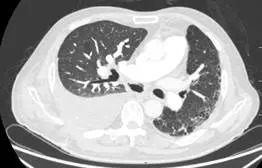

术后9天(6月19日)复查胸部CT(图2):肺移植术后,右侧胸腔少量积液,纵隔内可见极少量气体影(经反复阅片发现)。

图2